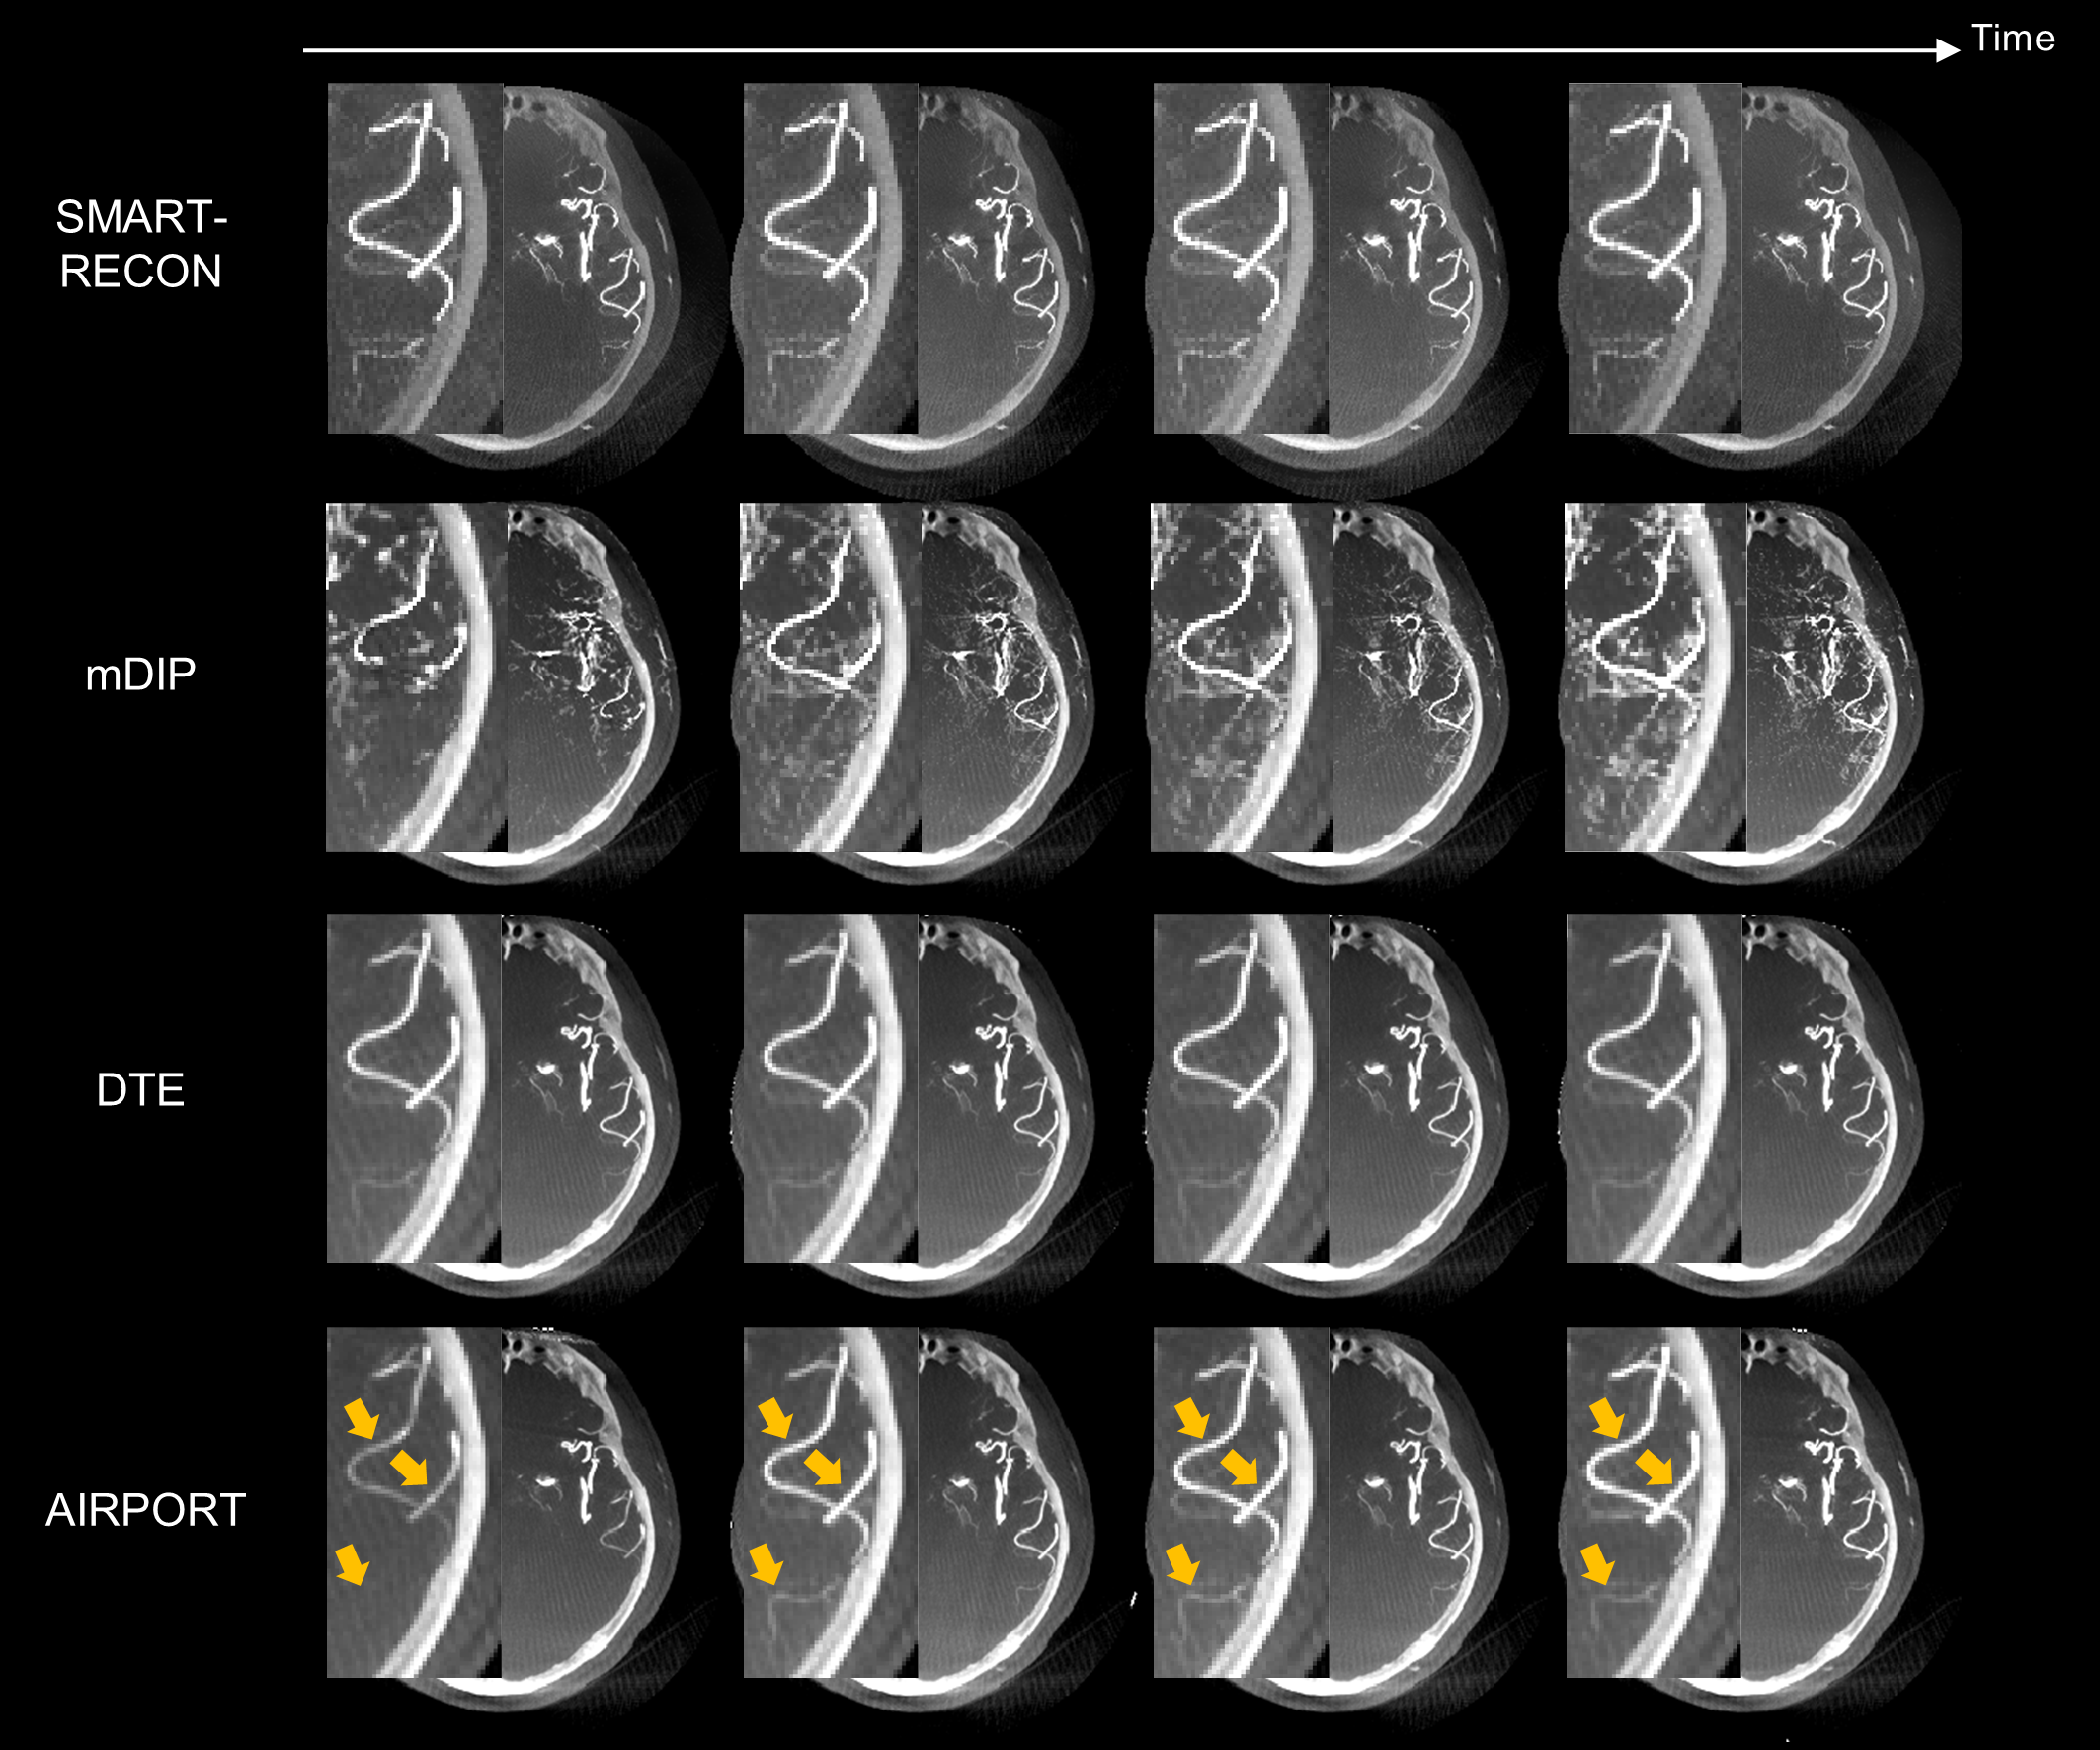

IEEE TMI | 高时间分辨CT成像

本文提出数据一致性约束的深度时间维度外插方法,利用数据一致性约束学习最优外插规则以提高时间分辨。

近日,beat365在线体育app医学人工智能研究中心、医学成像科学与技术系统(全国)重点实验室李印生研究员、梁栋研究员与上海联影医疗科技股份有限公司、首都医科大学附属北京天坛医院合作的高时间分辨CT成像研究成果,发表在国际医学成像顶刊IEEE Transactions on Medical Imag...